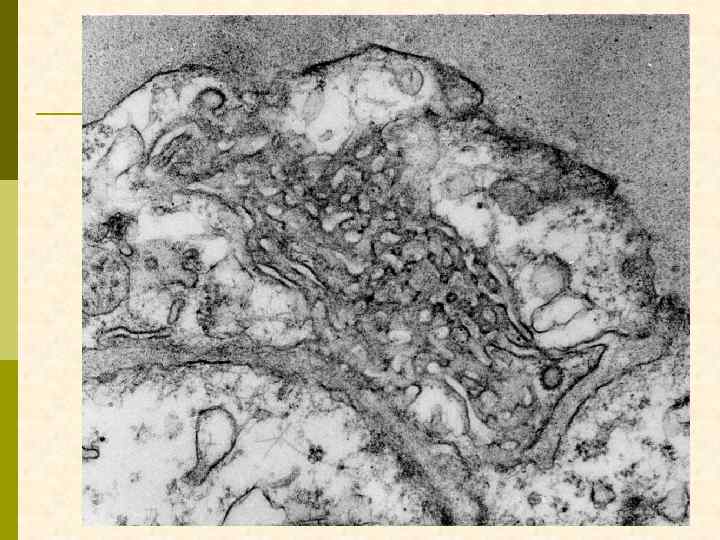

депозиты в мезангии и в ГБМ, тубуло-ретикулярные структуры в эндотелиоците

тубуло-ретикулярные структуры в эндотелиоците